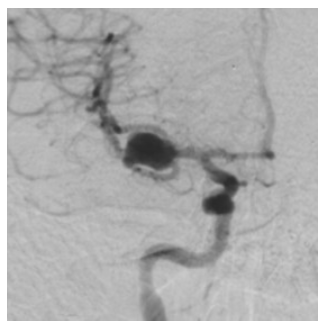

An urgent cerebral CT angiogram has been performed and an image from the CT is displayed.

The neurosurgical team wishes to urgently perform a craniotomy and clip a presumed ruptured right middle cerebral artery aneurysm.

image.png

What is your approach to assessing and managing the patient prior to surgery?